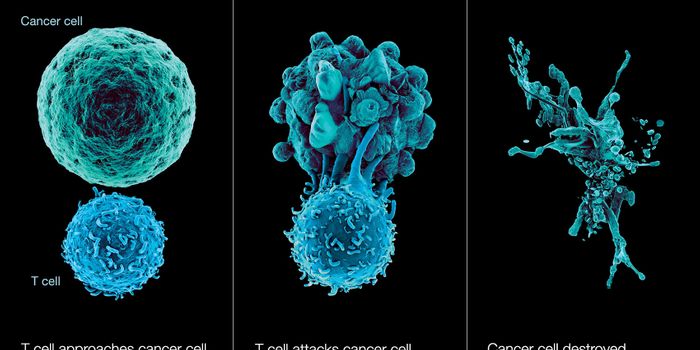

DEC 10, 2015ImmunologySuperior technology brings us novel images of cancer cells and lymphocytes this week, and now scientists can learn more ...

JUN 27, 2016ImmunologyT cells are the body’s natural fleet of cancer-attacking lymphocytes, but in recent years scientists have found a ...